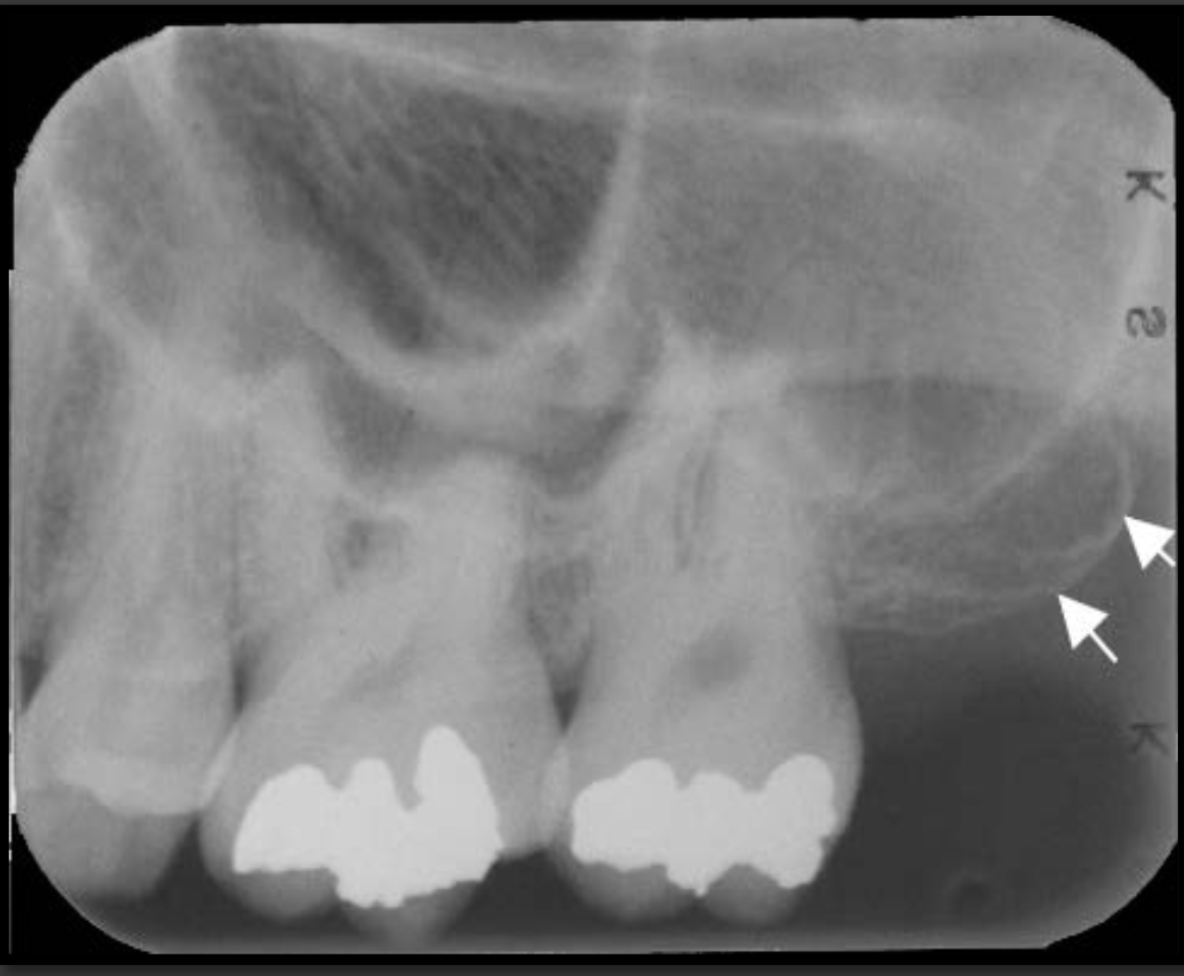

How does the floor of the maxillary sinus present in a radiograph?

It is a thin radio opaque line that travels low near the roots of the teeth.

How does the maxillary sinus present in a radiograph?

It is a radiolucent space that sits above the maxillary teeth.

Appears as a radiolucent area below the mandibular molars